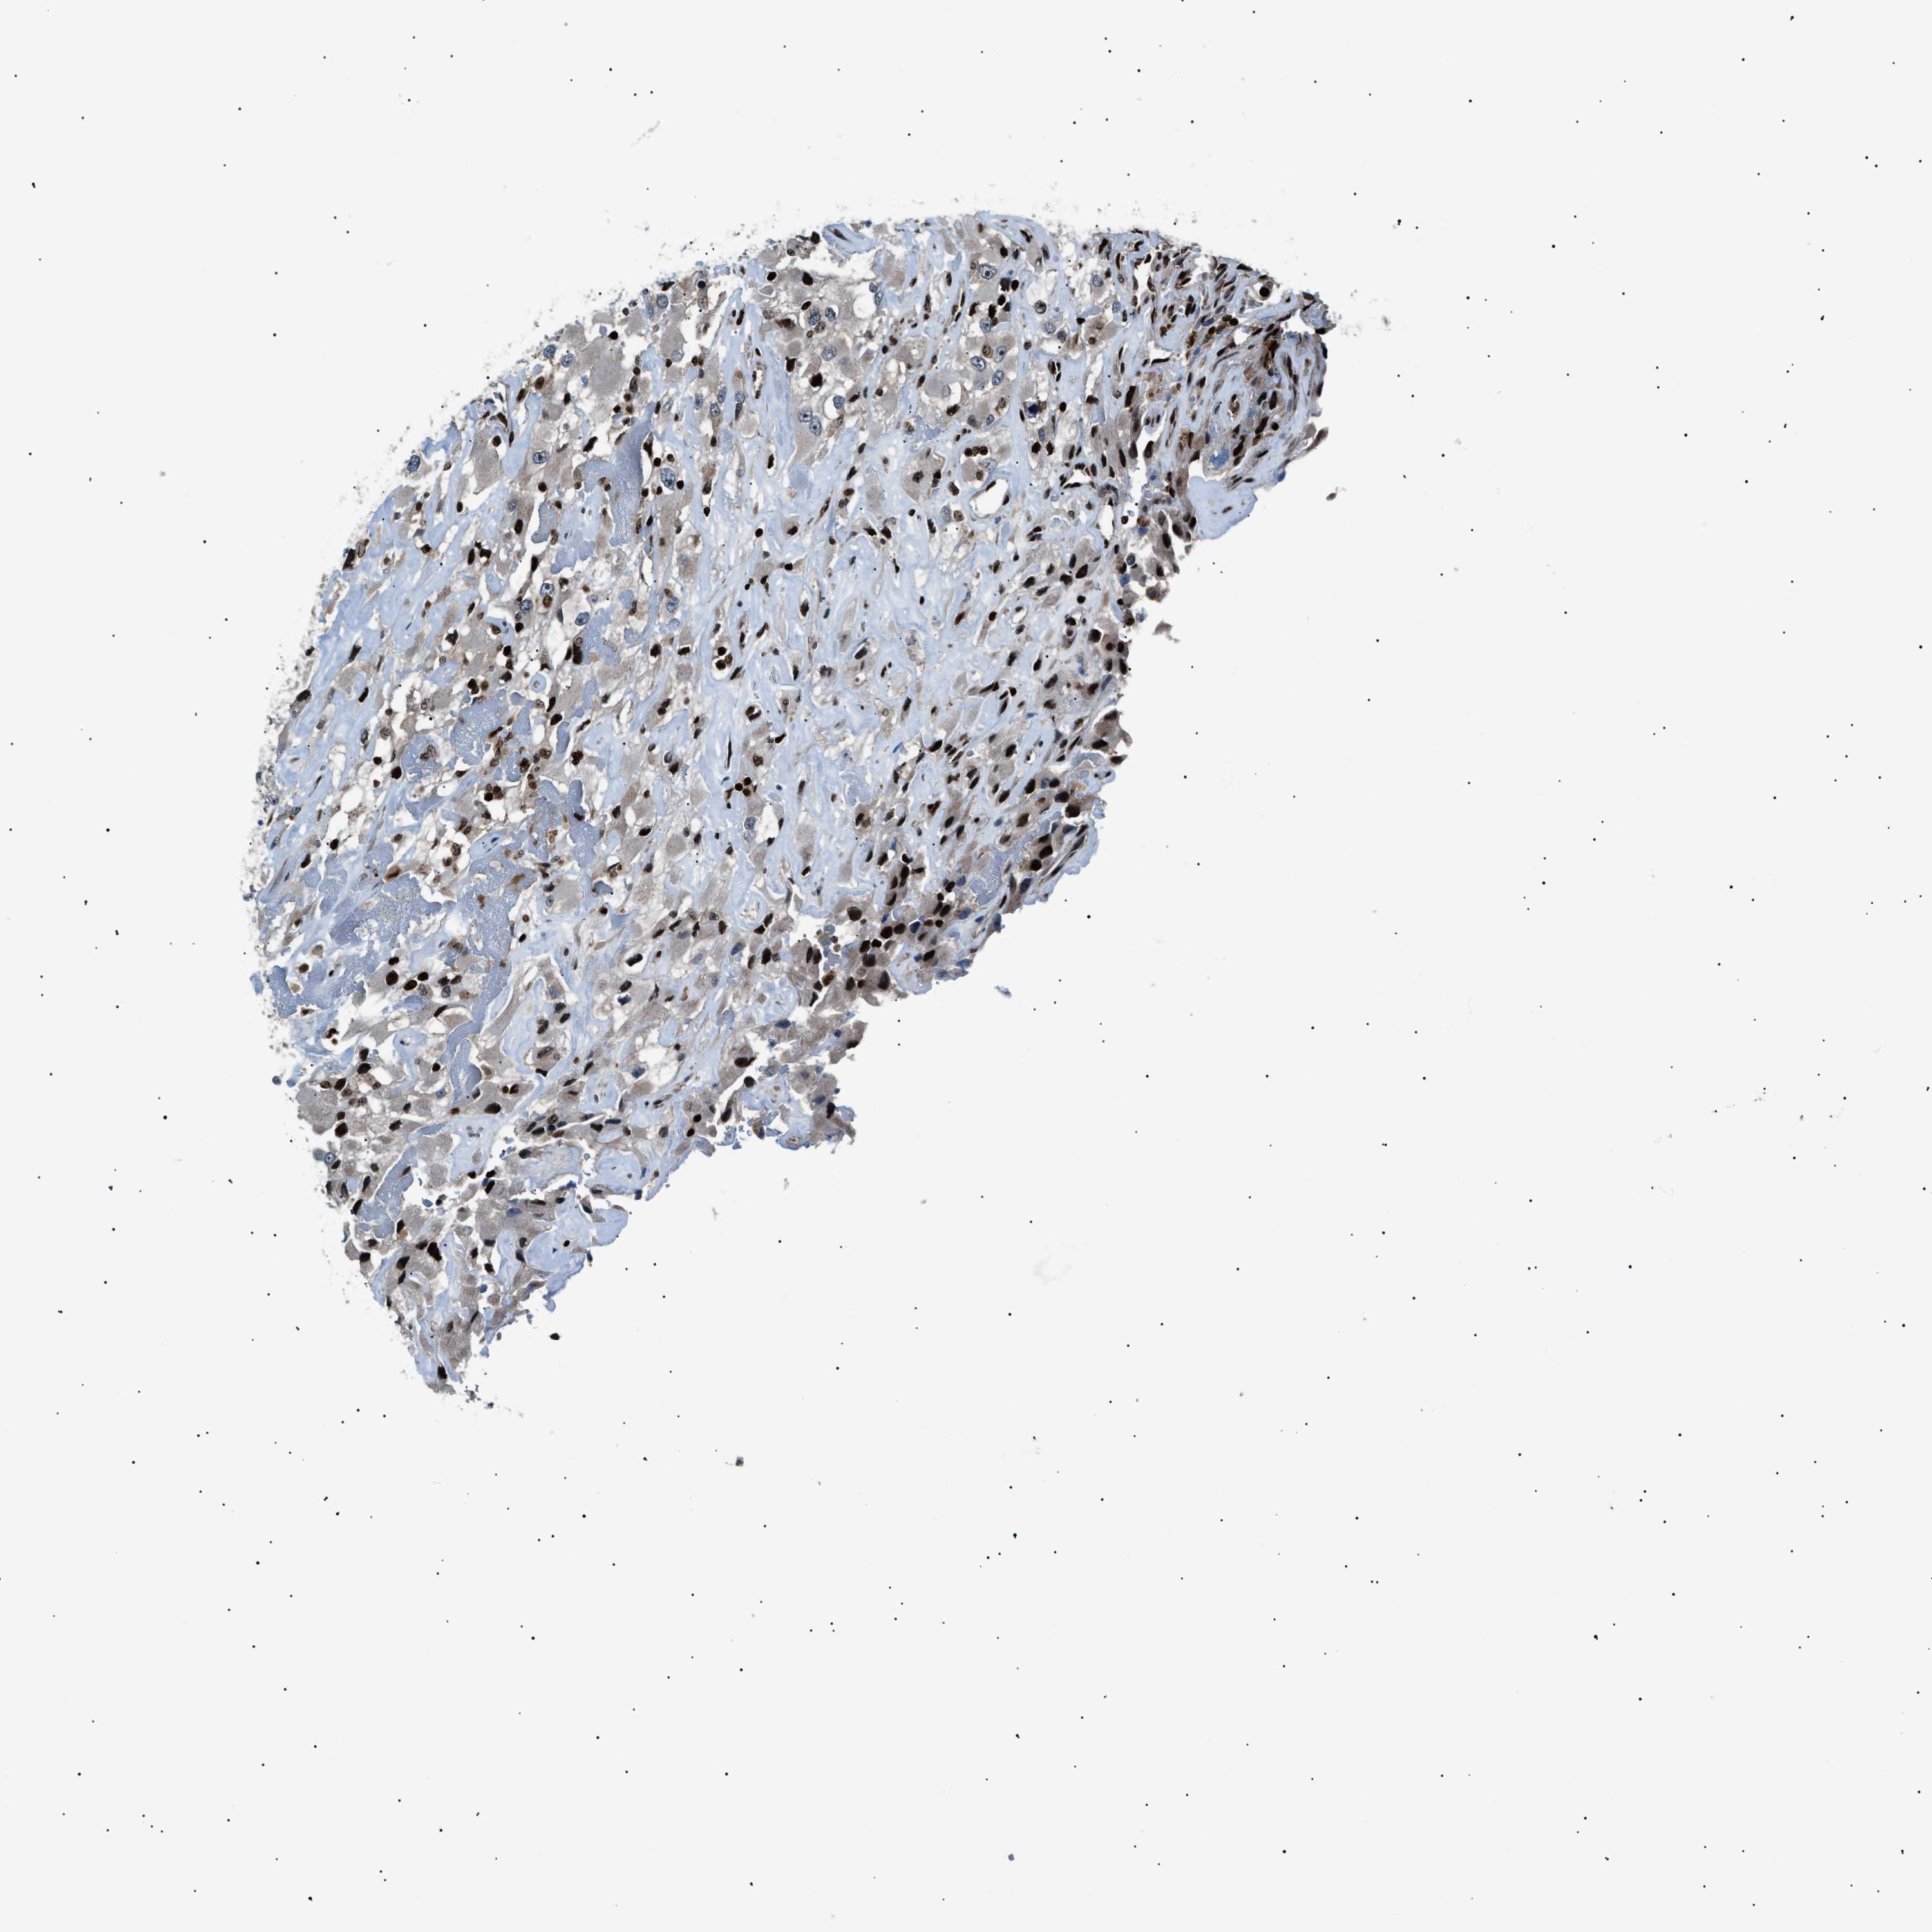

KIDNEY RENAL PAPILLARY CELL CARCINOMA (TCGA) - Interactive survival scatter ploti

The Survival Scatter plot shows the clinical status (i.e. dead or alive) for all individuals in the patient cohort, based on the same data that underlies the corresponding Kaplan-Meier plots. Patients that are alive at last time for follow-up are shown in blue and patients who have died during the study are shown in red.

The x-axis shows the expression levels (FPKM) of the investigated gene in the tumor tissue at the time of diagnosis. The y-axis shows the follow-up time after diagnosis (years). Both axes are complimented with kernel density curves demonstrating the data density over the axes. The top density plot shows the expression levels (FPKM) distribution among dead (red) and alive patients (blue). The right density plot shows the data density of the survived years of dead patients with high and low expression levels respectively, stratified using the cutoff indicated by the vertical dashed line through the Survival Scatter plot. This cutoff is automatically defined based on the FPKM cutoff that minimizes the p-score. The cutoff can be changed by dragging the vertical line or by entering a cutoff value in the square labeled "Current cut-off".

Under the Survival Scatter plot the p-score landscape (black curve; left axis) is shown together with dead median separation (red curve; right axis). Dead median separation is the difference in median mRNA expression between patients who have died with high and low expression, respectively. It is calculated as follows: median FPKM expression of dead patients with high expression - median FPKM expression of dead patients with low expression. This is intended to aid the user in visually exploring custom cutoffs and the associated p-scores and dead median separation.

Individual patient data is displayed and can be filtered by clicking on one or more of the category buttons on the top of the page. Categories describing expression level and patient information include: high, low, alive, dead, female, male and tumor stages. The scale of the x-axis can be toggled between linear and log-scale by clicking on the "x log" button. Mouse-over function shows TCGA ID, patient information and mRNA expression (FPKM) for each patient.

& Survival analysisi

Kaplan-Meier plots summarize results from analysis of correlation between mRNA expression level and patient survival. Patients were divided based on level of expression into one of the two groups "low" (under cut off) or "high" (over cut off). X-axis shows time for survival (years) and y-axis shows the probability of survival, where 1.0 corresponds to 100 percent.

PRKX is not prognostic in Kidney Renal Papillary Cell Carcinoma (TCGA)

Best expression cut offi

Based on the FPKM value of each gene, patients were classified into two groups and association between prognosis (survival) and gene expression (FPKM) was examined. The best expression cut-off refers the FPKM value that yields maximal difference with regard to survival between the two groups at the lowest log-rank P-value. Best expression cut-off was selected based on survival analysis .